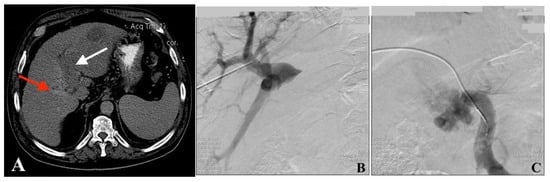

Figure 1.

Images from a 60-year-old male patient diagnosed with HCC complicated with PVTT. (A) Axial CT image shows that the HCC lesion completely occupied segments 2 and 3, the left PV is obliterated by the tumor thrombus (white arrow), while the right PV remains patent (red arrow). (B) VesOpen procedure images in succession—the portography “above” the thrombus (PAT) shows the right PV patent branches. (C) VesOpen procedure images in succession—the portography “below” the thrombus (PBT) shows a dilated SMV interrupted by the tumor thrombus at the level of PV confluence; the main PV is not opacified. (D) Tumor thrombus processing by bipolar endoluminal VesOpen RF device. (E) Adequate recanalization of the PV-obstructed segment is seen after stent implantation. (F) Follow-up CT image (5.5 months after the procedure). The patient did not receive any other treatment. The left lobe tumor shrinkage and the not-treated left PV recanalization (white arrow) are clearly documented—abscopal effect of PV tumor thrombus RF processing.